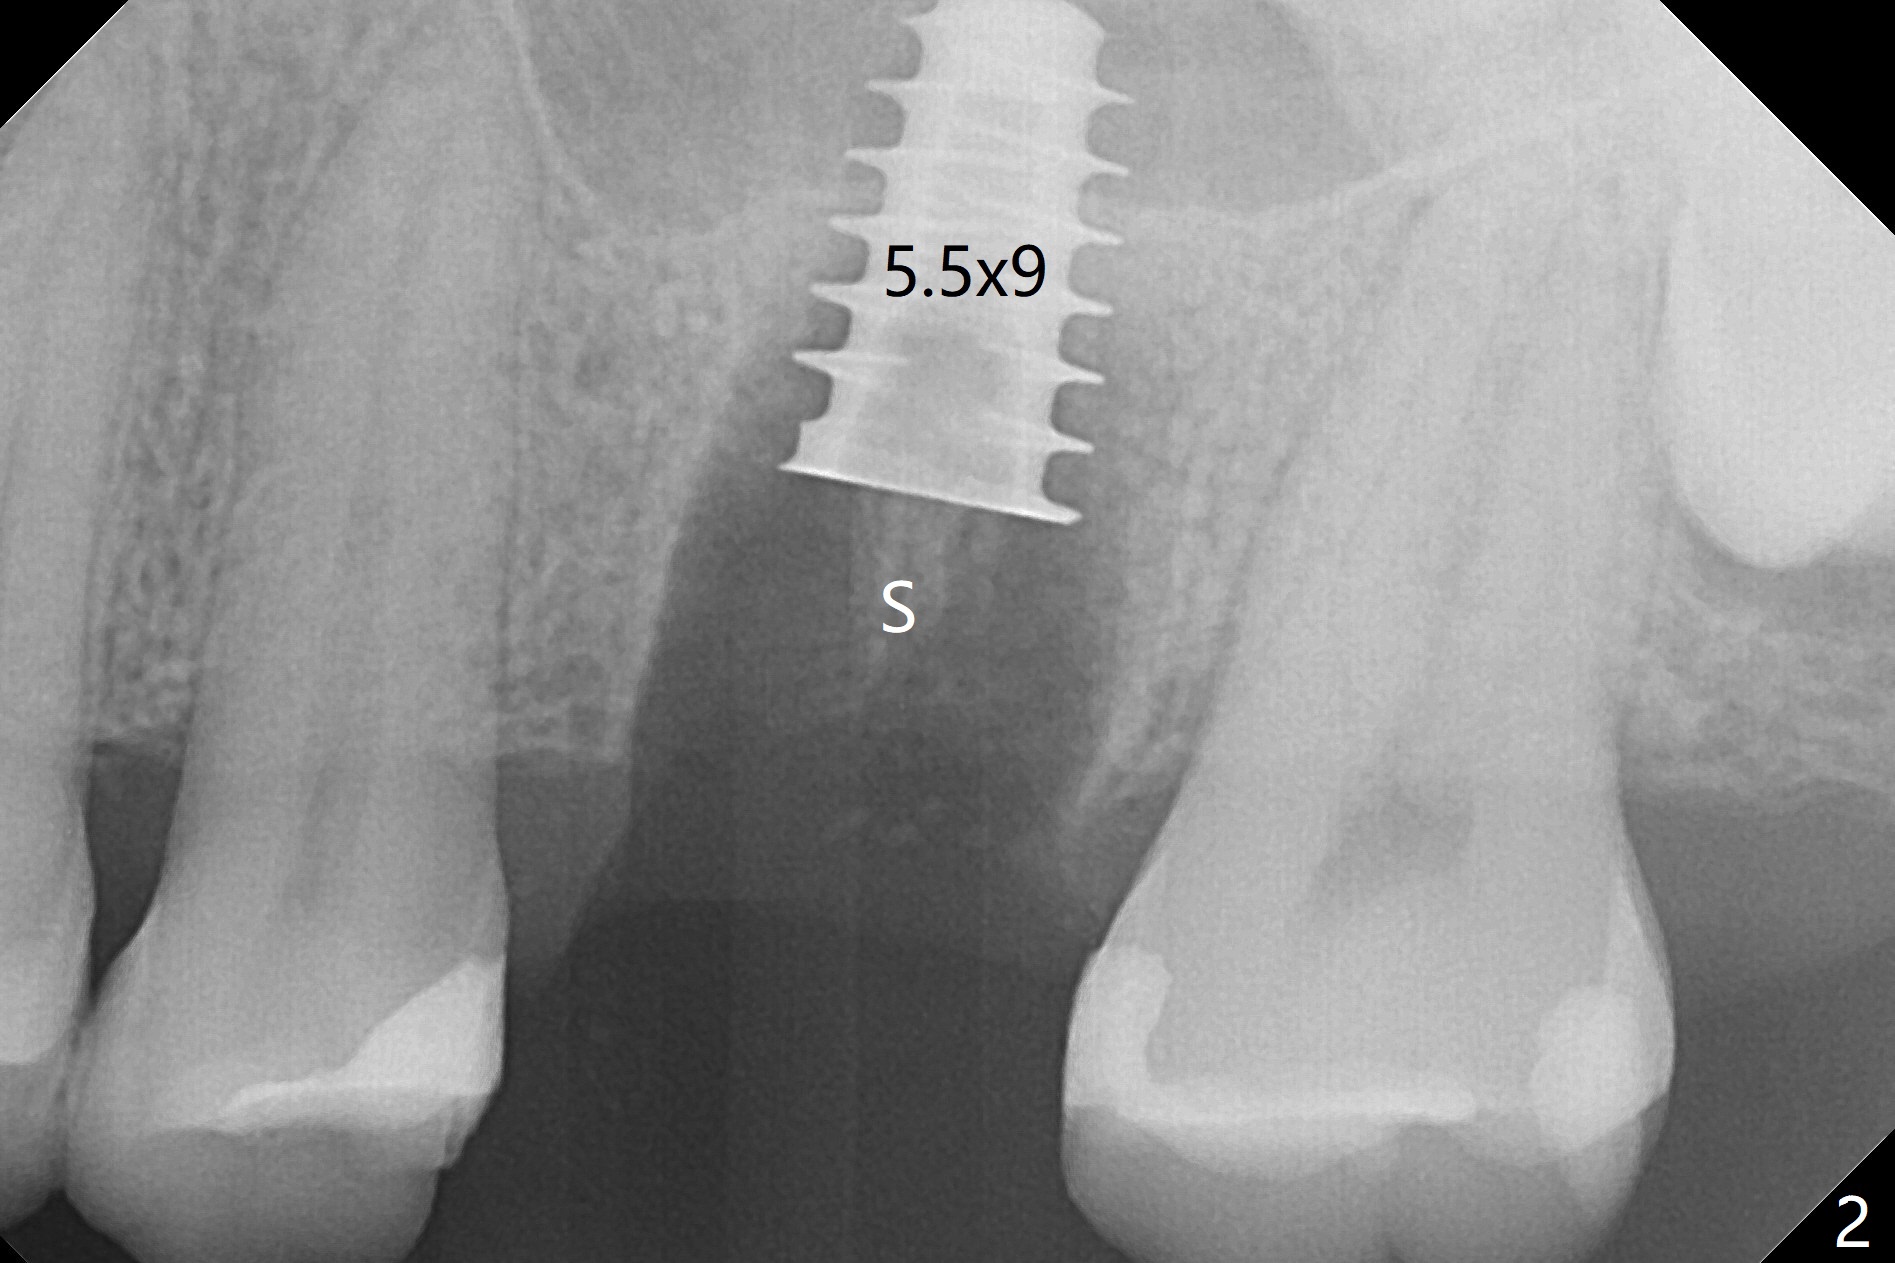

After extraction of the tooth #14 with palatal swelling (Fig.1 *), the septum (S in Fig.2) is found to be thin. Sequential osteotomy quickly deviates to the palatal socket. In spite of using Lindamann bur to remove the bone from the buccal portion of the osteotomy, the apical end of a 5x9 mm dummy implant slides into the palatal socket with the coronal end placed as buccal as possible for restoration (Fig.2 (poor trajectory)). Further use of Lindamann bur for buccal bone removal is not feasible, since the buccoapical portion of the osteotomy starts to be perforated with apparently intact sinus membrane. With insertion of Vanilla graft for sinus lift through the buccoapical portion of the osteotomy mentioned above, a 6x11 mm implant is placed with the same trajectory (Fig.2, <40 Ncm). With placement of a 6.5x4(3) mm abutment (off angle) and of Vanilla graft in the remaining sockets (Fig.2 *), periodontal dressing is applied. When the dressing is dislodged for the 2nd time (12 days postop with healing socket), an angled abutment 5x15 degree, 3 mm cuff, is placed and a provisional is fabricated. There is no sign of sinus infection. The provisional and angled abutment become loose without sinus infection 2 months postop. A 5.5x3 mm healing abutment is placed with light tenderness. If this case turns to be failure, do not stick an immediate implant from potentially infected socket into the sinus in the future. The socket appears to heal 11 months postop (Fig.4). Later a 5x4(3) mm abutment is placed for final restoration. The palatal margin is low. The abutment screw is loose <2 months post cementation, probably due to deep placement and poor trajectory (buccal). It becomes loose again 4 months later. Prior to retightening, a 6 mm profile drill is used. BW shows no bony interference (Fig.5 (opposing tooth occlusal wear; bruxism)), while PA shows the buccal bone, suggesting poor trajectory. The abutment is loose for the 3rd time 17 months post cementation. When the crown/abutment is removed, the hex is worn. After proximal reduction, the crown/abutment feels to be unable to be re-seated. When the crown is sectioned, the abutment itself is incompletely seated (Fig.7,8). The mesial crest appears to interfere with seating (Fig.8). When the 5.2x3 mm dummy abutment is seated, the buccal margin is subgingival, while the palatal one supragingival, suggesting the buccally tilted implant (guided surgery essential). A 4.5x4(4) mm pair abutment seems to be seated completely (Fig.9). The hex of the 5x4(3) mm abutment is worn, but the abutment seems to be able to be seated completely (Fig.11), although not so crisply (easily) as the unworn one clinically. Return to Upper Molar Immediate Implant, Prevent Molar Periimplantitis (Protocols, Table), Armaments Screw Xin Wei, DDS, PhD, MS 1st edition 06/26/2018, last revision 12/20/2020